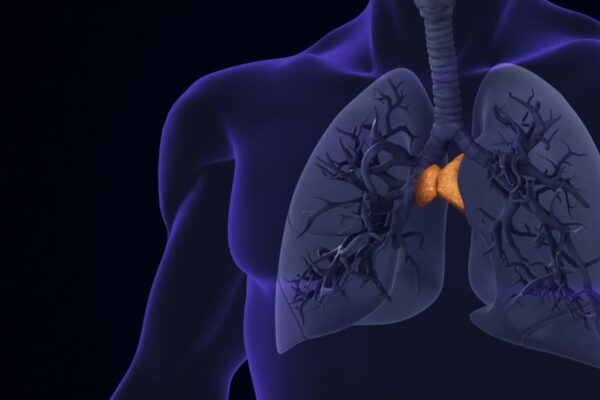

“İşe yaramaz” deniyordu ama gerçek farklı: Uzun yaşamın gizli anahtarı bulundu

Araştırmalar, uzun süredir işlevsiz kabul edilen timus bezinin aslında kanserden kalp sağlığına kadar birçok alanda hayati rol oynadığını gösterdi. Tıp literatüründe uzun süredir ergenlikten sonra körelen ve “işlevsiz” hale gelen bir yapı olarak kabul edilen timus bezi, modern teknolojinin yardımıyla yeniden mercek altına alındı. Mass General Brigham araştırmacıları tarafından yürütülen ve yapay zeka algoritmalarıyla desteklenen iki yeni çalışma,…